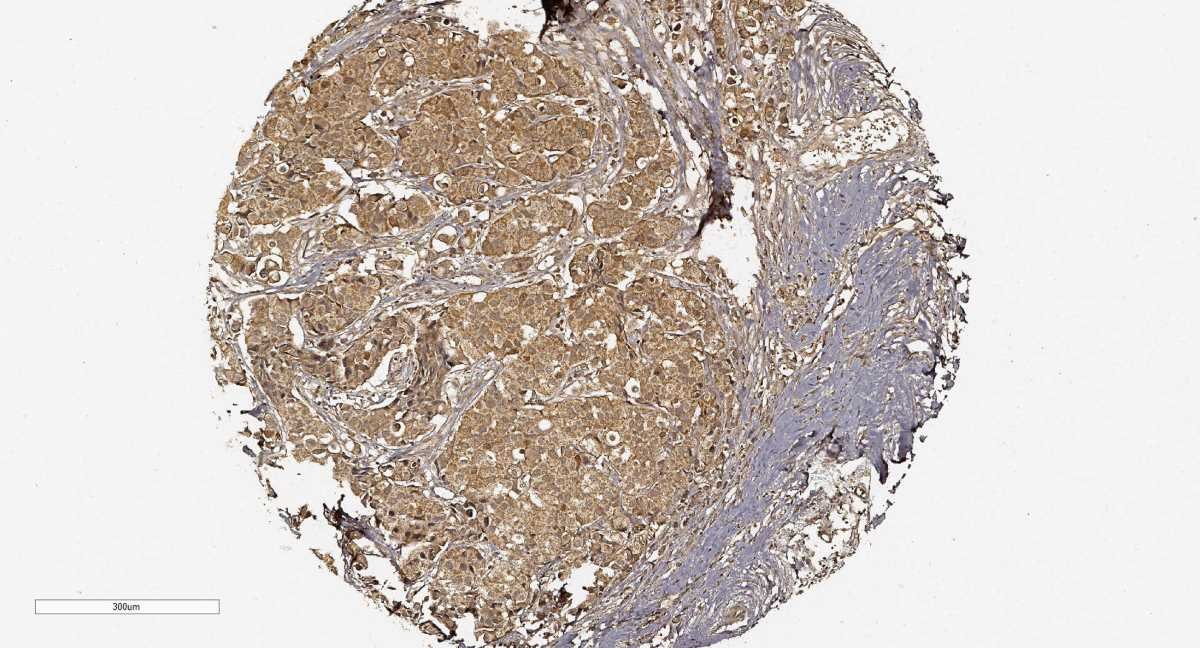

Gráfico de un complejo proteico con un gran potencial de frenar el crecimiento del cáncer de mama descubierto por un equipo internacional de investigadores, entre ellos del español Juan Cadiñanos, director científico de la Fundación Centro Médico de Asturias. Crédito: Treekitkarnmongkol y otros.

Un equipo internacional de investigadores, entre los que se encuentra el español Juan Cadiñanos, descubrió una nueva diana terapéutica contra el cáncer de mama que abre nuevas posibilidades de tratamiento. El hallazgo, que recoge este martes la revista de la Asociación Americana para el Avance de la Ciencia (AAAS, por sus siglas en inglés), describe el papel fundamental que desempeña un conjunto de proteínas a la hora de frenar la multiplicación de las células tumorales en determinados tipos de cáncer de mama. Los investigadores ya habían desvelado previamente que hay una serie de tumores de mama que presentan niveles altos de una proteína denominada Aurora A, implicada en la división celular y, por tanto, en la multiplicación del cáncer, explica a EFE Cadiñanos, director científico de la Fundación Centro Médico de Asturias. La paradoja es que aunque se habían diseñado fármacos para inhibir la proteína Aurora A e impedir la evolución de los tumores, los resultados de los ensayos clínicos “no habían sido muy positivos”. La novedad de esta investigación es el descubrimiento de una agrupación de varias proteínas formadas por supresores tumorales, que disminuyen los niveles de Aurora A, y la capacidad de reproducción del cáncer. En ese complejo proteico, los científicos identificaron una proteína en concreto, llamada PTEN, que es un potente supresor tumoral.

Un freno al cáncer

“Hemos hallado un freno al cáncer de mama”, subrayó el científico español. El equipo de Cadiñanos ya comprobó en experimentos con ratones modificados genéticamente que si perdían la proteína PTEN aparecían tumores de mama y niveles elevados de Aurora A, en un hallazgo que recogió la revista Nature Genetics en 2017. Otros autores del presente estudio, como Subatra Sen y Hirosi Katayama (investigadores del centro MD Anderson de Texas), habían visto los mismos resultados con muestras celulares humanas cultivadas en laboratorio: a menor niveles de PTEN más posibilidades de descontrol de la proteína Aurora A y del desarrollo de los tumores de mama asociados a su sobreexpresión. Ahora, tras comprobar el potencial conjunto de PTEN y otras proteínas, los investigadores demostraron, en ensayos con ratones, que la combinación de dos fármacos: Alisertib, para inhibir la actividad de Aurora A, y Fimepinostat, para favorecer su degradación, da muy buenos resultados para suprimir el crecimiento de los tumores de mama. Mientras ambos fármacos no son de gran eficacia por separado, la combinación de ambos se demostró exitosa en ensayos preclínicos. “Siempre se van a requerir ensayos adicionales, pero esta combinación de fármacos abre nuevas posibilidades de tratamiento y estrategias terapeúticas en los cánceres de mama con sobreexpresión de Aurora A”, aseveró Cadiñanos. EFE